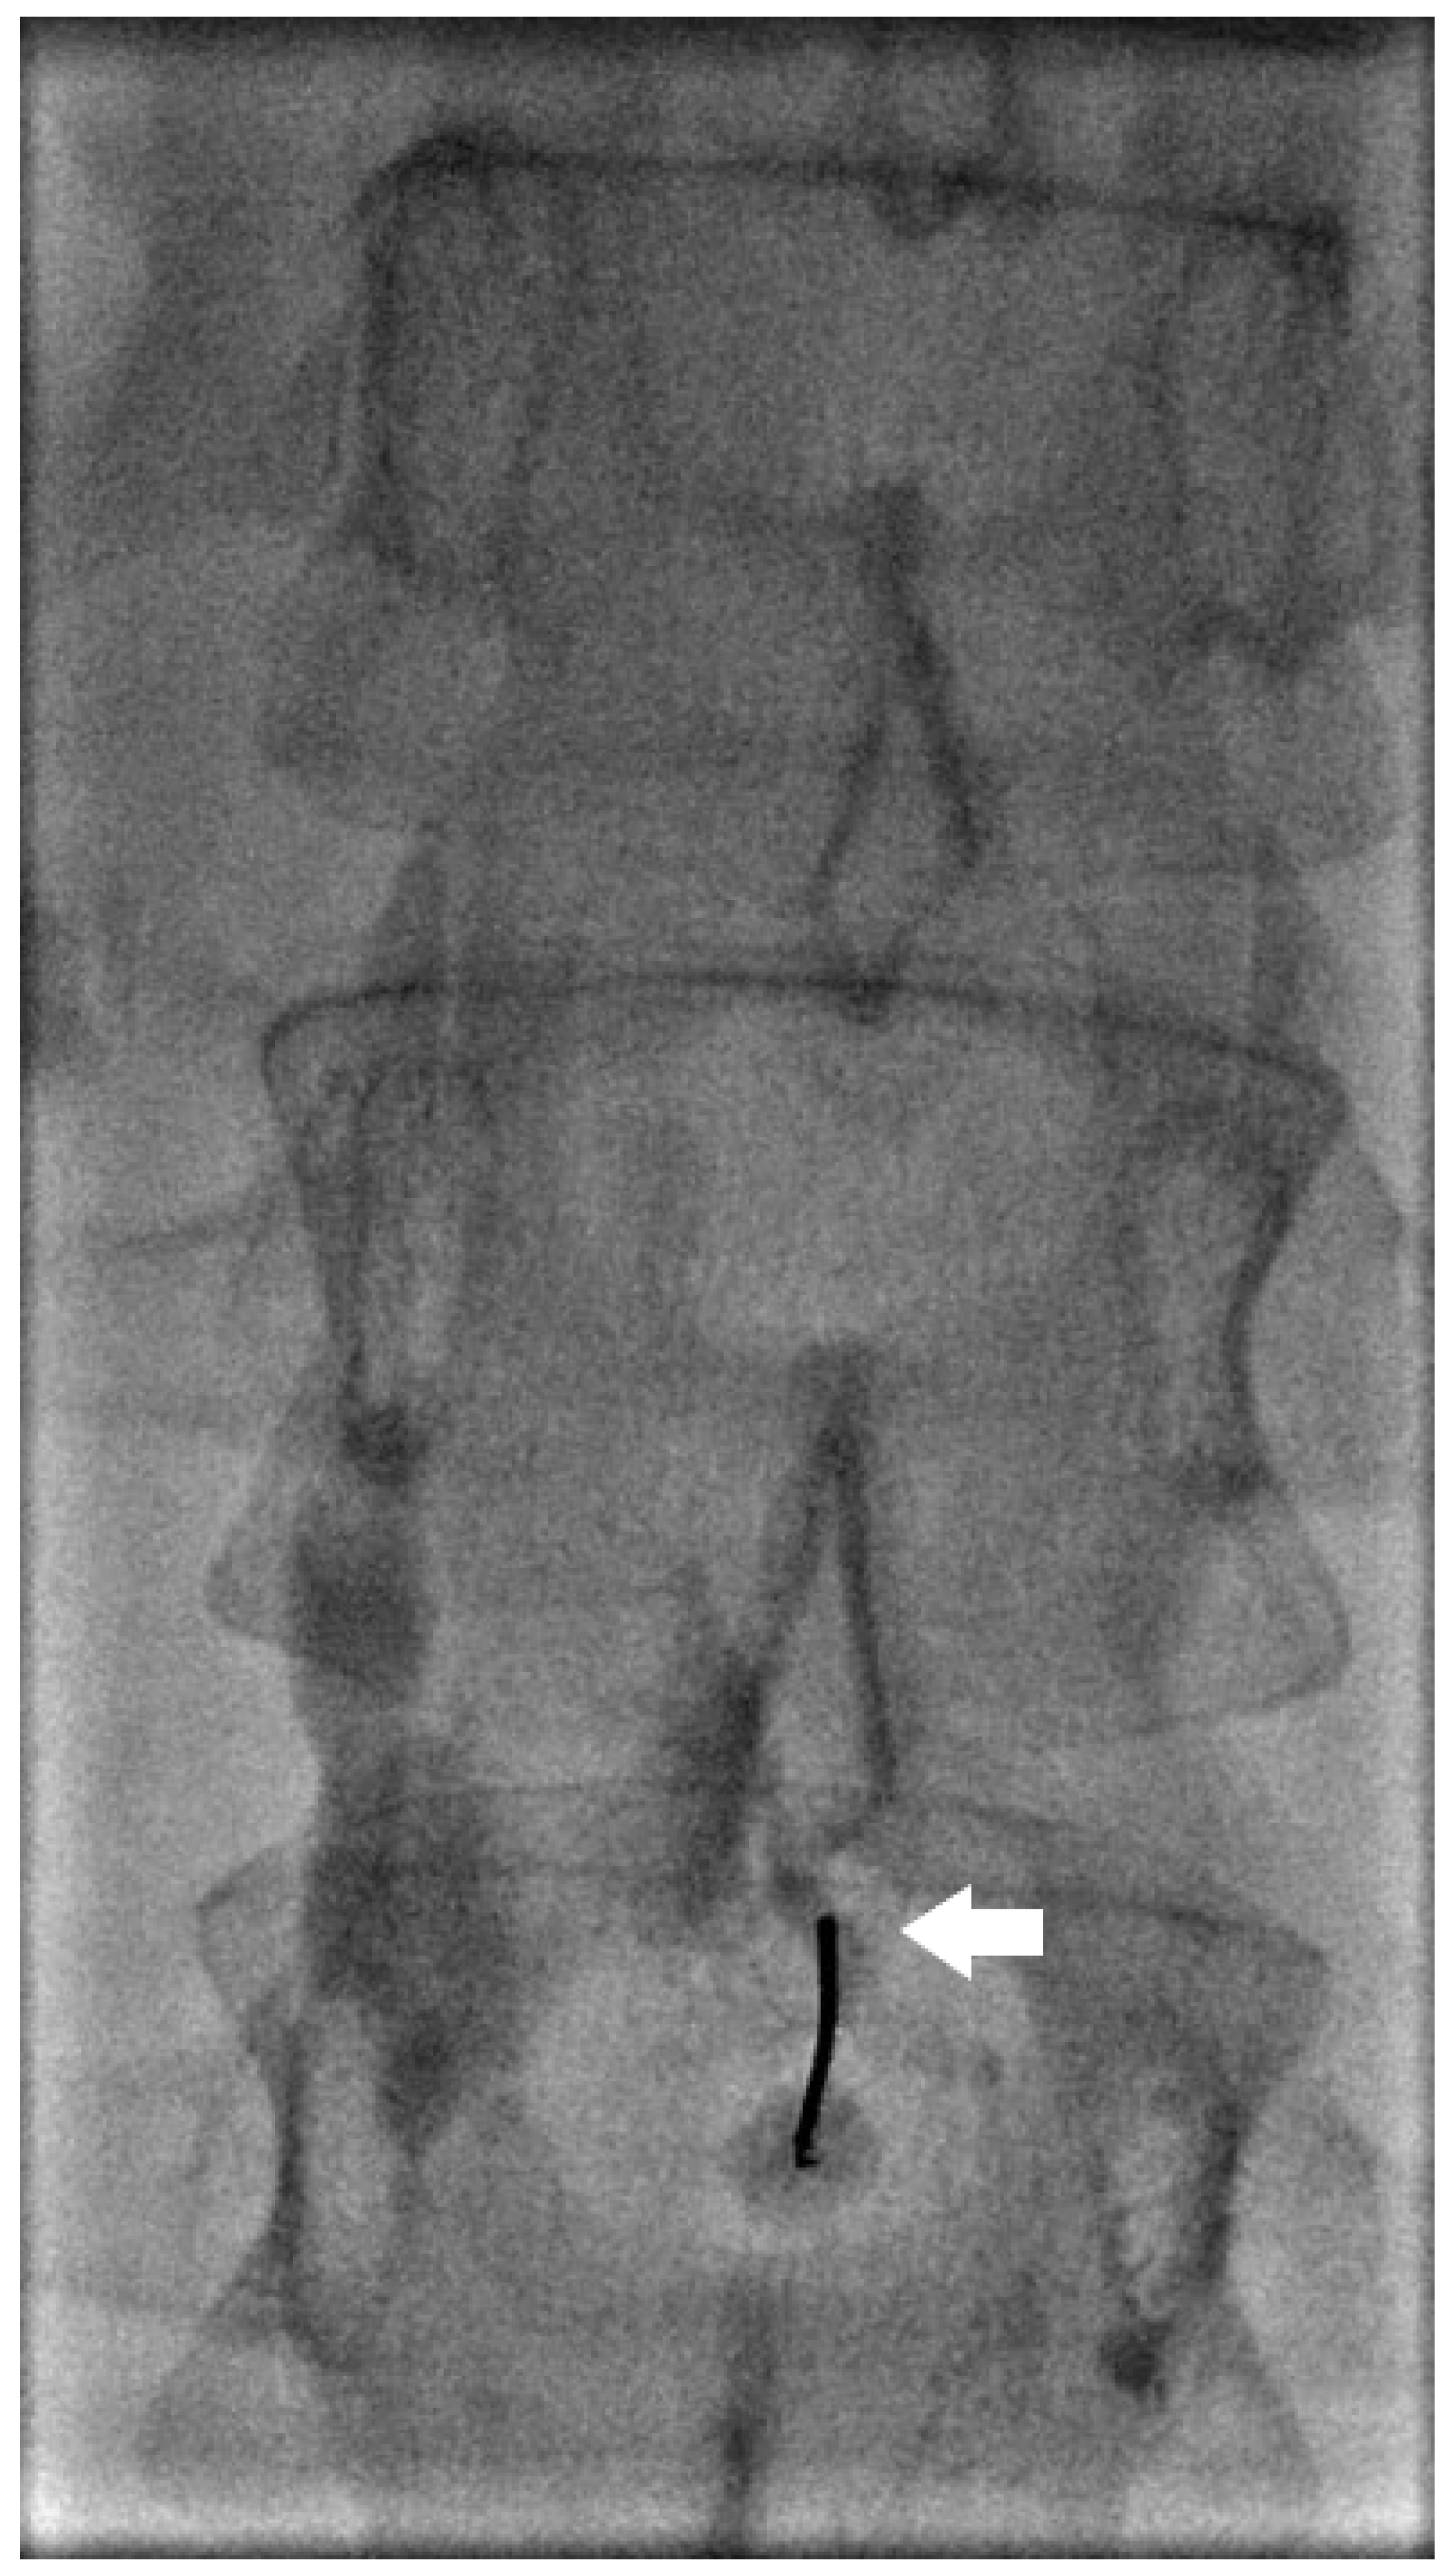

Following INL, embolization is often performed to address identified leak points. This process typically involves accessing the lymphatic system through a larger needle (20–22 G) under imaging, confirming proper positioning by flushing with 5% dextrose, and then employing various embolization techniques (Figure 2). The most common embolic agent is n-butyl cyanoacrylate (nBCA) in varying dilutions with lipiodol. Proper contrast opacification is crucial to identify leak points and exclude potential shunts.

Figure 2.

Spot image the same patient in Figure 1 with a 22-gauge needle placed under fluoroscopy into the site of the lymphatic leak (arrow) prior to embolization.